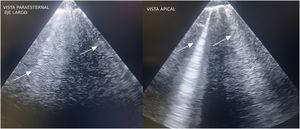

Ecografía pulmonar: absceso pulmonar secundario a neumonía necrotizante

Luis Javier Pérez Bazaga, Carlos Ávila Sansegundo, María Ángeles Santiago Triviño

Med Intensiva. 2024;48:244-5